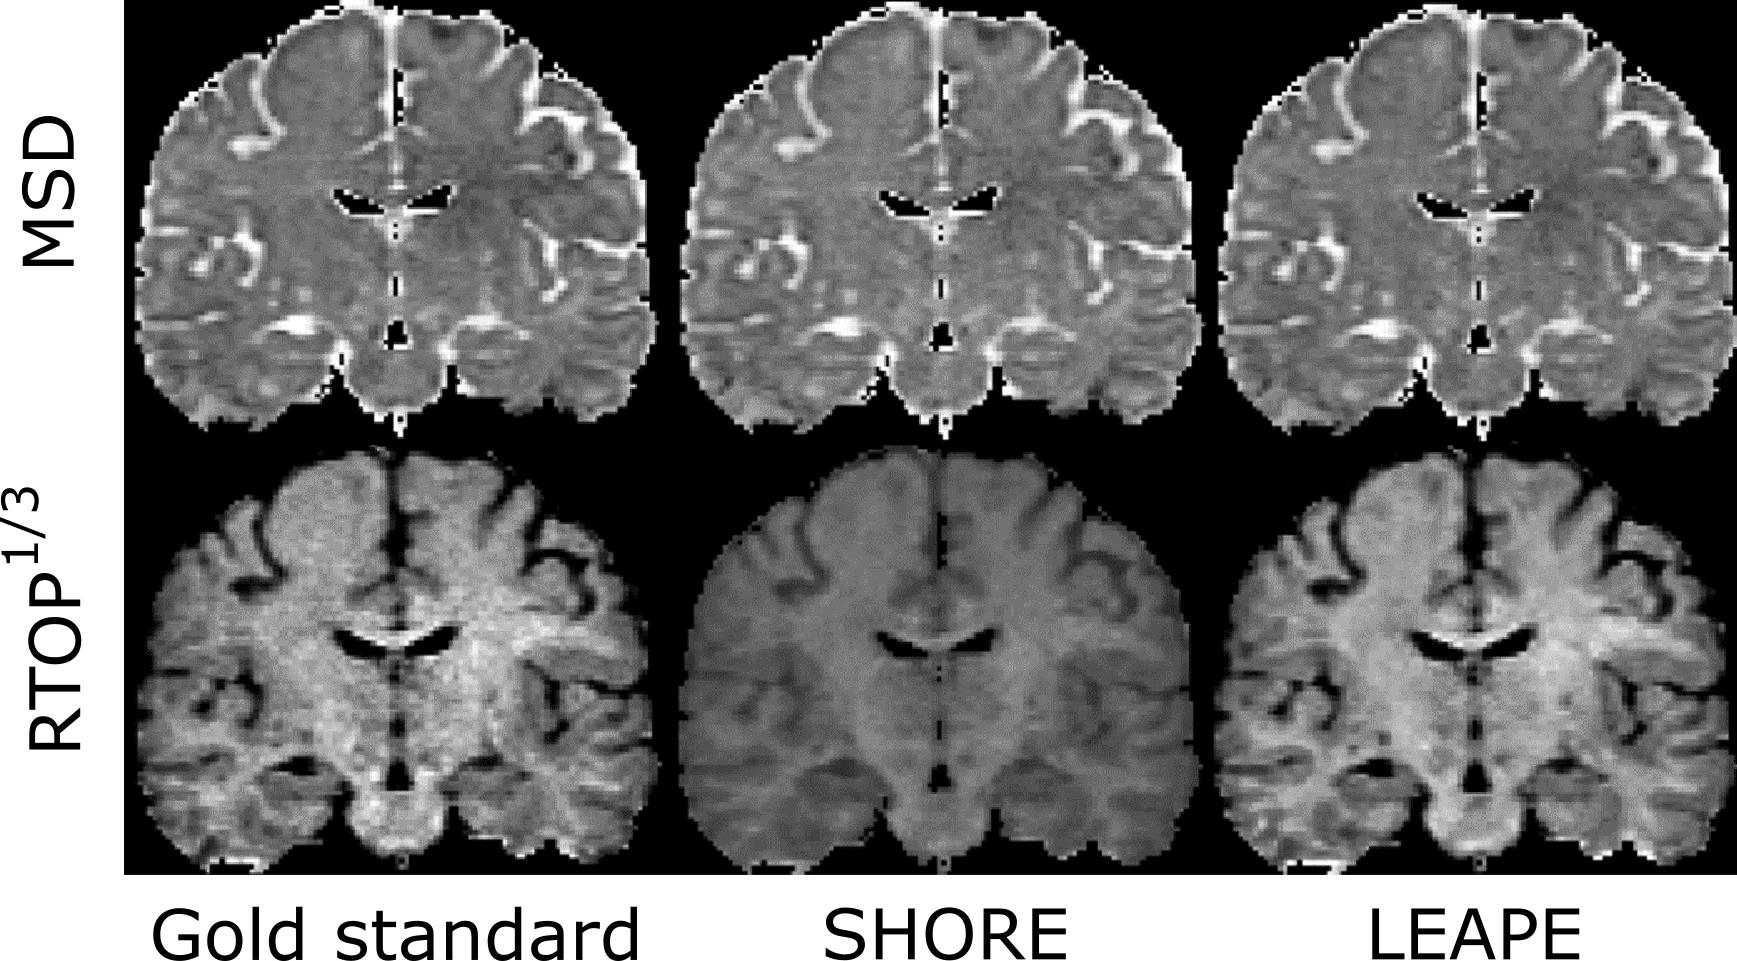

First, we evaluated the EAP estimation by examining the scalar features: MSD and RTOP. The LEAPE results on a representative subject are shown and compared with the gold standard and the results obtained by the conventional SHORE method [8] in a coronal slice in Fig. 3. Note that here for each MSD or map, the color map is the same for the three columns. The LEAPE results resemble the gold standard. The RTOP result of SHORE is remarkably biased with the smaller set of diffusion gradients. Then, we computed the average disagreement in the brain between the estimates and gold standard for the ten subjects, which is shown in the boxplots in Fig. 4. For both MSD and , the LEAPE errors are smaller than those of SHORE, and the differences are highly significant () using a paired Student’s -test.